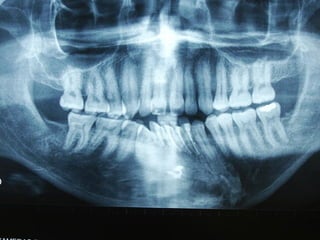

Queratoquiste odontogénico

Otro caso